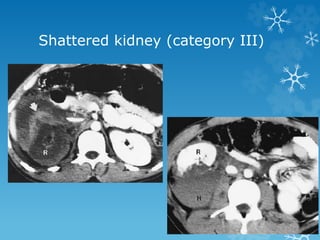

Shattered kidney (category III)

Grade 1 Contusion or contained and non -expanding

Grade 5 Pedicle injury or avulsion of renal hilum that

devascularizes the kidney; completely shattered

kidney;